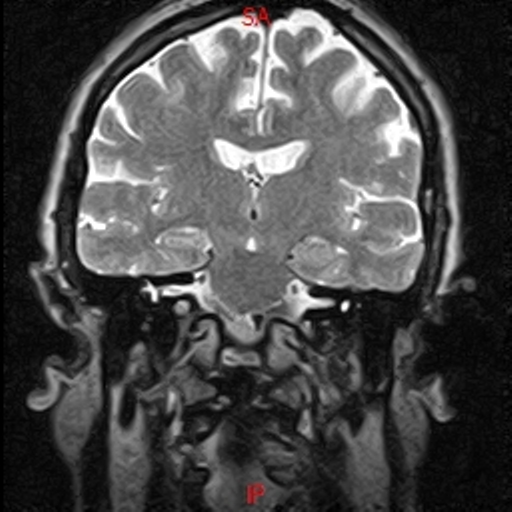

• Resonancia NORMAL CRANEAL FLAIR CORONAL

• Resonancia NORMAL CAIS T2 CORONAL